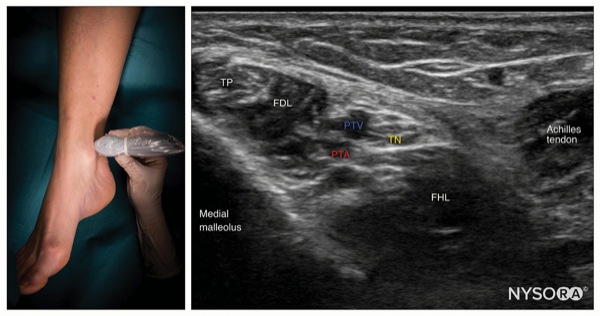

To Block the Tibial Nerve

Place the transducer in a transverse orientation between the medial malleolus and Achilles tendon (Figure 1).

Identify the tibial nerve as an oval hyperechoic structure next to the posterior tibial artery and veins, deep to the flexor retinaculum.

Insert the needle using an in-plane or out-of-plane approach toward the fascia enveloping the nerve (Figure 2).

Inject 1 to 2 mL of local anesthetic to confirm proper needle position by observing the spread into the fascial plane containing the nerve and surrounding the nerve.

Complete the block with a volume of 5 to 7 mL.